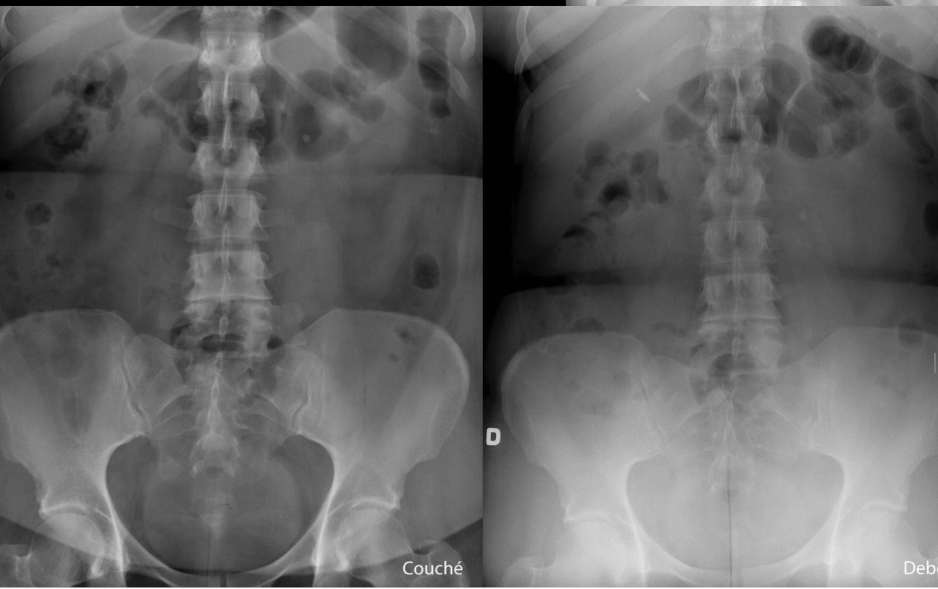

Q

donne le diagnostic complet

A

Obstruction colique avec valvule illéo caecale incompétente